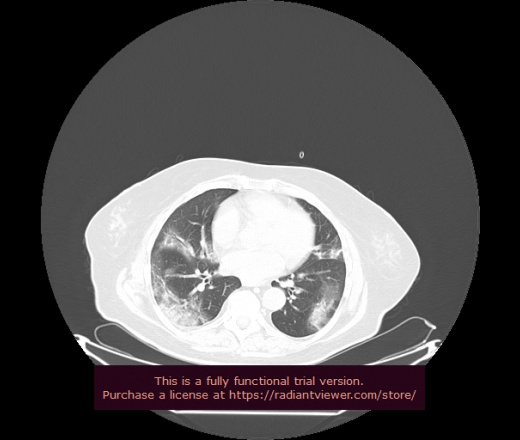

Уважаемые коллеги, если имеется интерес, сможете ли Вы спрогнозировать дальнейшее +-одинаковое течение процесса у 4 данных разных пациентов? Зацепиться где-то можно очень просто, где-то нельзя.

3 ID:88438